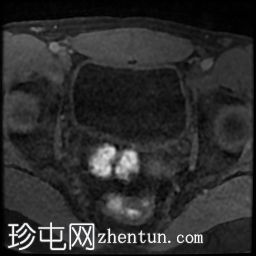

轴位

DWI

4.jpg

前列腺大小为32.8 x 41.5 x 34.7 mm(前后径 x 宽度 x 头尾径),体积为25.88 ml,属于正常范围。前列腺中央可见一逗号状囊性占位性病变,大小为17.3 x 12.1 x 9.3 mm(头尾径 x 前后径 x 宽度)。可见囊肿与前列腺尿道相通。囊内未见可疑内容物——具体而言,未见囊内出血或碎屑——弥散加权成像结果为阴性,提示无囊内感染。